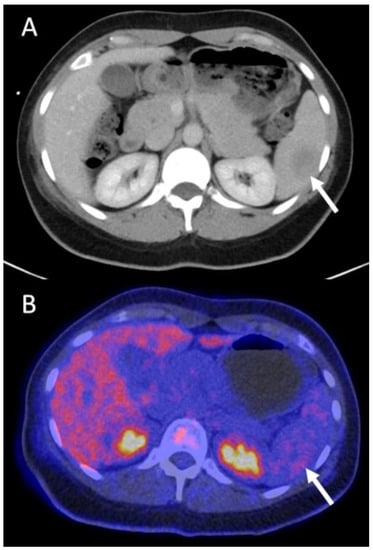

3.4.3. Recurrence Patients (n = 20/52)

| Group C Recurrence (n = 20 scans in 19 patients) | Stage I: n = 4 Stage II: n = 10 Stage III: n = 3 Stage IV: n = 2 | non-treatment | systemic | C | P | recurrence | yes, invasive | 1 | Major (n = 9) | earlier therapy start with improved outcome, avoidance of invasive tests |

| recurrence | yes, not specified | 1 | earlier therapy start with improved outcome, avoidance of invasive tests | |||||||

| surgery | systemic | C | P | recurrence | yes, not specified | 1 | better customized therapy, avoidance of additional tests | |||

| P | P | yes, invasive | 1 | better customized therapy, avoidance of invasive tests | ||||||

| systemic | surgery + systemic | C | C | recurrence | yes, not specified | 1 | earlier therapy start with improved outcome, avoidance of additional tests | |||

| C | C | no | 1 | earlier therapy start with improved outcome | ||||||

| P | P | no | 1 | earlier therapy start with improved outcome | ||||||

| systemic + RTX | non-treatment | P | C | no recurrence | yes, invasive | 1 | avoidance of unnecessary therapy and its side effects, avoidance of invasive tests | |||

| systemic + RTX | surgery + systemic | P | C | recurrence | yes, not specified | 1 | better customized therapy, avoidance of additional tests | |||

| systemic | systemic (modified) | P | P | recurrence | yes, not specified | 1 | Minor (n = 8) | better customized therapy, avoidance of additional tests | ||

| yes, invasive | 1 | better customized therapy, avoidance of invasive tests | ||||||||

| non-treatment | non-treatment | C | C | no recurrence | yes not specified | 3 | avoidance of additional tests | |||

| yes, invasive | 1 | avoidance of invasive tests | ||||||||

| systemic | systemic | P | P | recurrence | yes, not specified | 1 | avoidance of additional tests | |||

| yes, non-invasive | 1 | avoidance of additional tests | ||||||||

| systemic | systemic | C | C | no recurrence | no | 1 | No change (n = 3) | |||

| systemic | systemic | P | P | recurrence | no | 2 | ||||